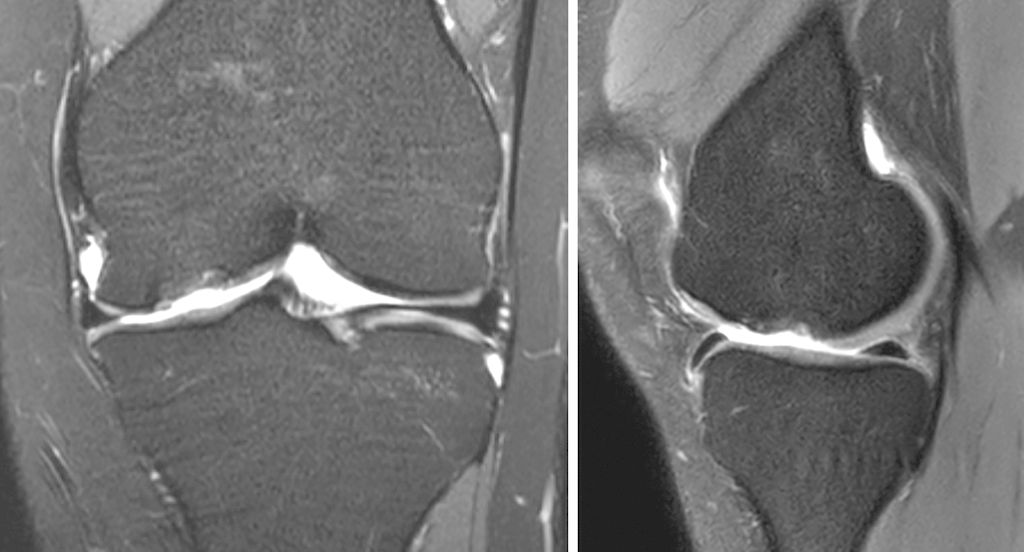

Abb. 1a und b: MRI-Bildgebung präoperativ bei grossem, vollflächigem Knorpelschaden an der medialen Femurkondyle einer jungen Patientin